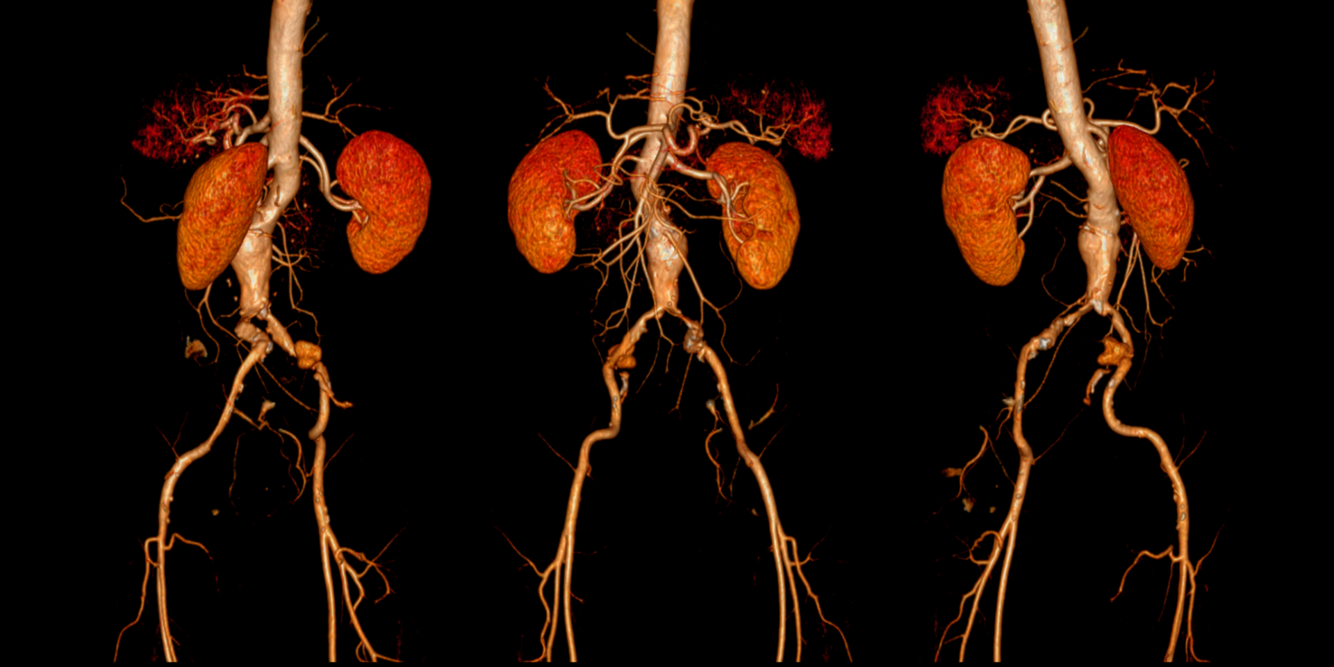

AAA | ABDOMINAL AORTIC ANEURYSM

men>66 / women >70 / European descent

COPD / family history / hyperlipidaemia / hypertension / smoking / coronary,cerebrovascular or peripheral arterial disease

abrupt onset of abdo/back pain, cardiovascular collapse / loss of conciusness

abdo aorta diameter > 3cm (5.5cm high rupture risk)

single abdo ultrasound

3-4.4cm | small aneurysm | 12mo rescan

4.5-5.4cm | medium aneurysm | 3mo rescan

>=5.5cm | large aneurysm | refer within 2weeks to vascular surgery for intervention OR EVAR (elective endovascular repair) OR if ruptured open repair